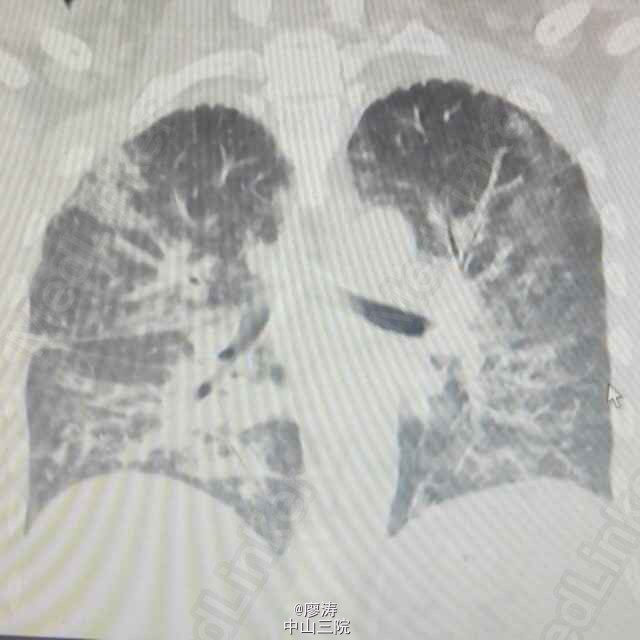

患者肾移植术后3月余,发热6小时入院,CT检查双肺弥漫性实变,呈“毛玻璃状”,CMV抗体检查阳性,诊断为巨细胞病毒性肺炎。给予抗病毒、抗细菌和吸氧等辅助治疗。肾移植术后服用免疫抑制剂,抵抗力降低,容易发生机会性感染。其中最严重死亡率最高的就是巨细胞病毒感染(CMV),死亡率高达60%以上,好发于肾移植术后三周左右。